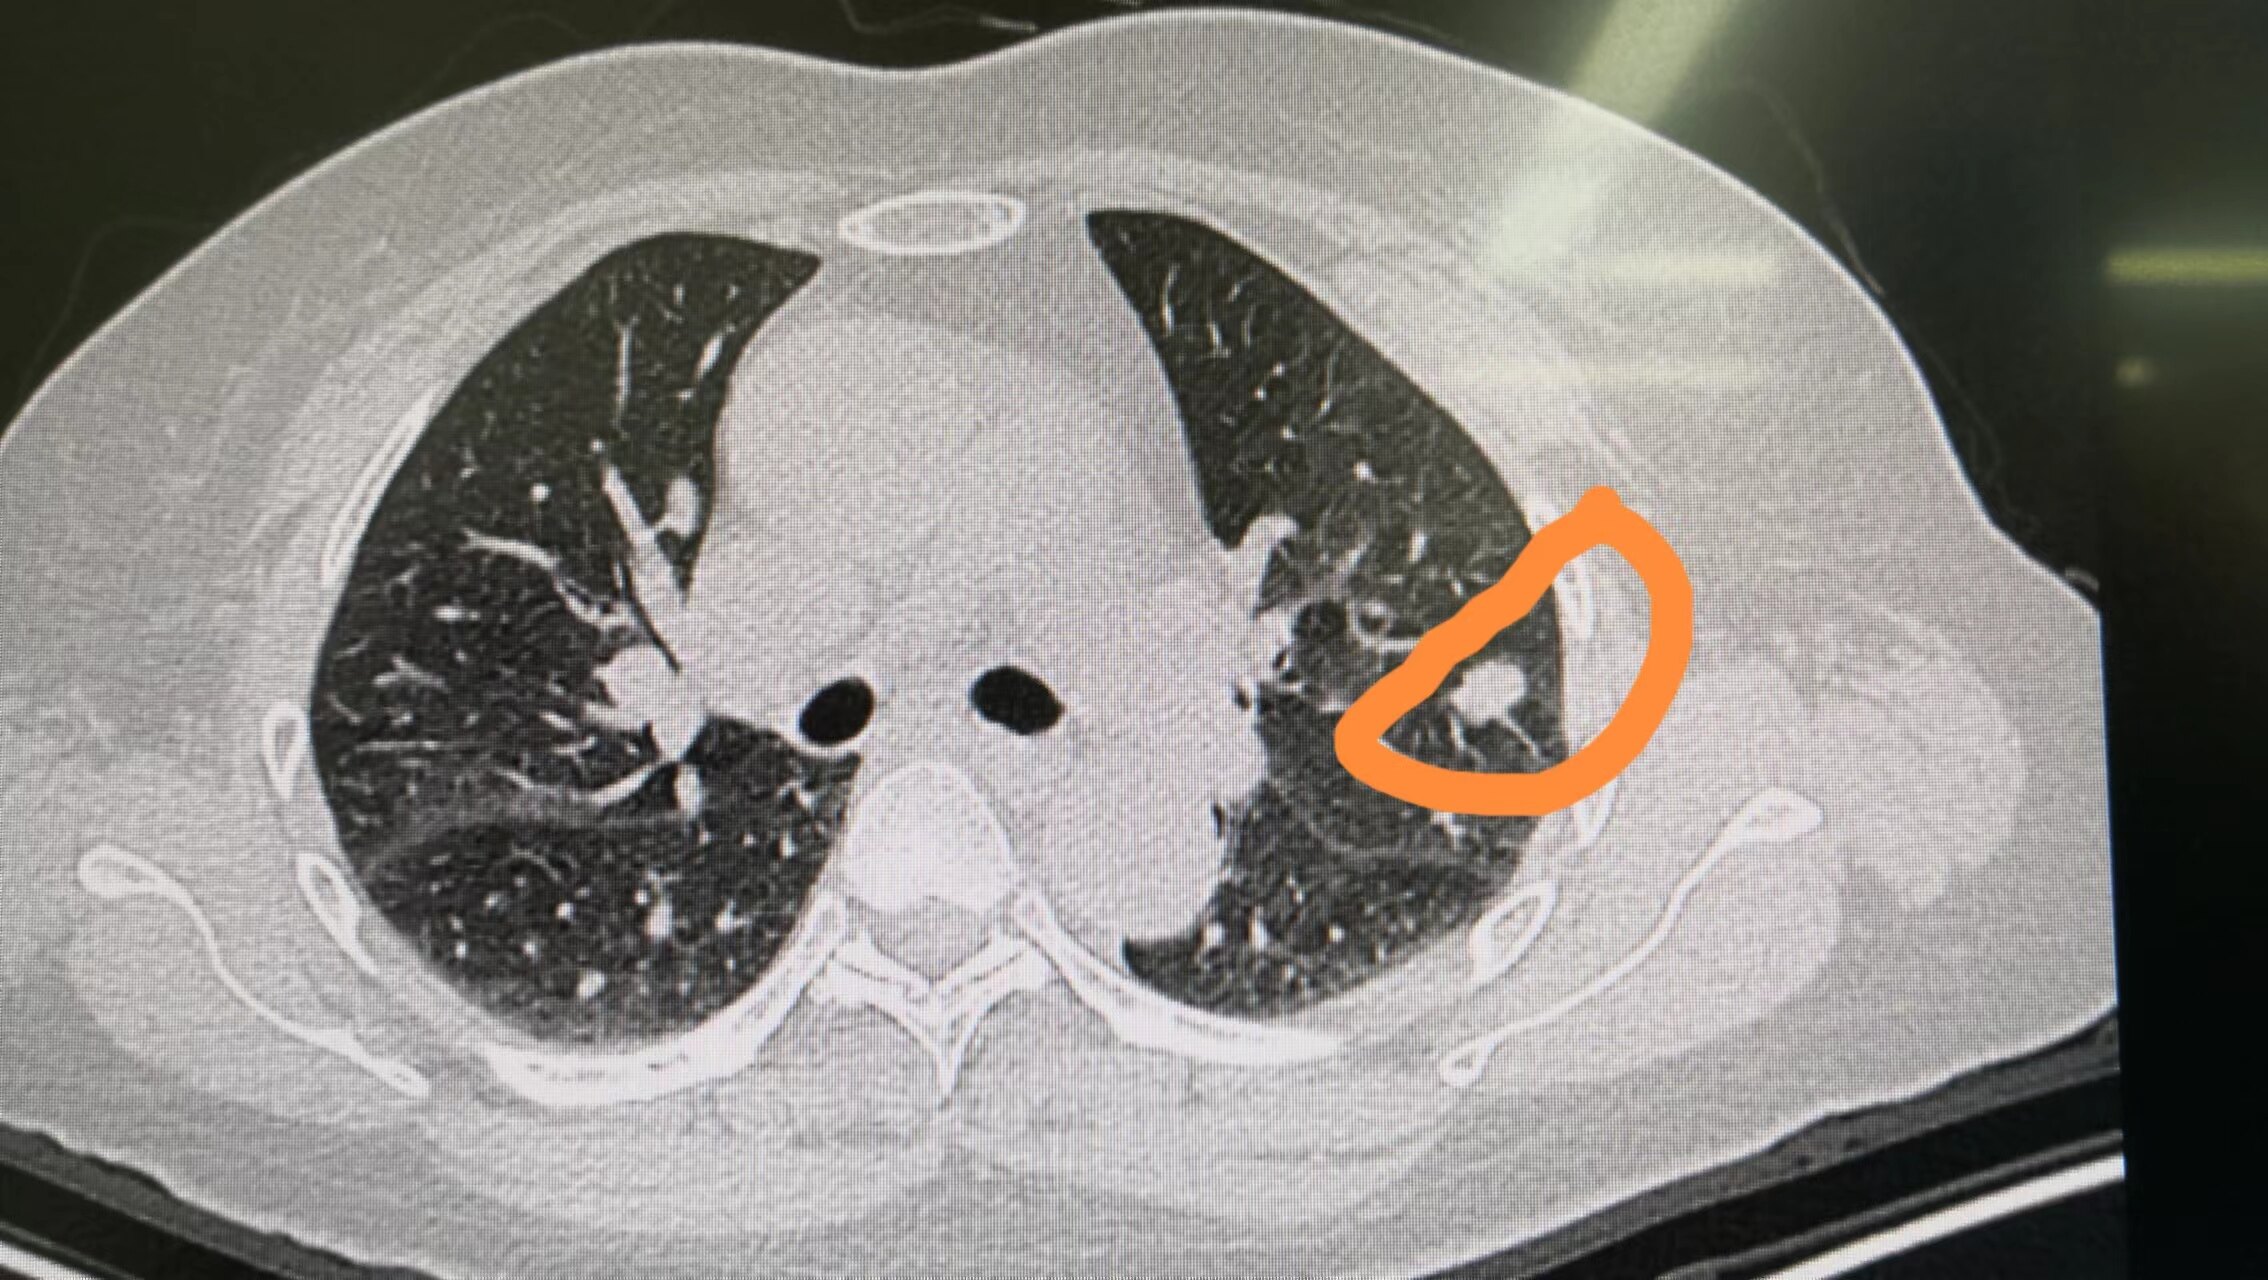

现在,没有研究阐明多发磨玻璃病变比单发更凶险,预后更差;若果是恶性病变,不论单发还是多发,害处都大。对多发性病变,首先规避每位病变剖析良恶性或许,剖析原则类似单发囊肿。现有研究阐明,这种多发的磨玻璃病变并非癌症广泛转移,而是多个原发病灶。多发磨玻璃病变患者接受放疗摘除后,其预后仅与主病变相关,即与最大病变有关,它的病理分期就会影响病人的生存。为此,多发肿块病人的预后并不一定会差于单发病变的病人,主病变恶性程度低、分期早的多发肿块病人也可以有良好的生存预期。

疑惑七:怎样处理发觉的肺多发磨玻璃病变?

对于肺多发磨玻璃病变的处理,应依照个体化治愈的原则。依据病患年纪、身体健康状况、预期寿命、病灶部位、数量、大小等状况,拟定针对性的治愈、随访方案。例如,对于高龄、体弱多病、合并其他慢性肝病或恶性脑瘤、预期生存期超过10年的多发磨玻璃病变病人,眼科放疗医治可能并不是最佳选择,放疗带给的外伤或风险有或许超过了其治愈疗效。假如对于一个没有上述问题,临床上高度担心病变恶性的病人,在不显著影响病人生活品质的前提下,能完全放疗摘除的行放疗摘除,放疗方法可以选择多处楔形摘除术,或肺段摘除术,或鼻窦摘除术。对两侧不同声带的多发肿块,视病人身体情况、心肺功能贮备状况行同期或分期放疗医治。不能完全一次性摘除所有可疑恶性病变时,优先处理主病变,以消除最大恐吓。对考虑为不典型增生样囊肿或原位癌的次病变,为保留肺功能,可选择暂不切掉,紧密随访观察。对因身体条件难以耐受放疗或不愿手术的多发磨玻璃病变病人,可以选择立体定向放射医治等手术方式。

其实,肺多发磨玻璃病变在临床上并不罕见,仍具备惰性生长的特性,其预后并不一定比单个磨玻璃病变差。治愈方式以骨科放疗和精准手术为主,优先处理最大、最具恐吓的主病变。